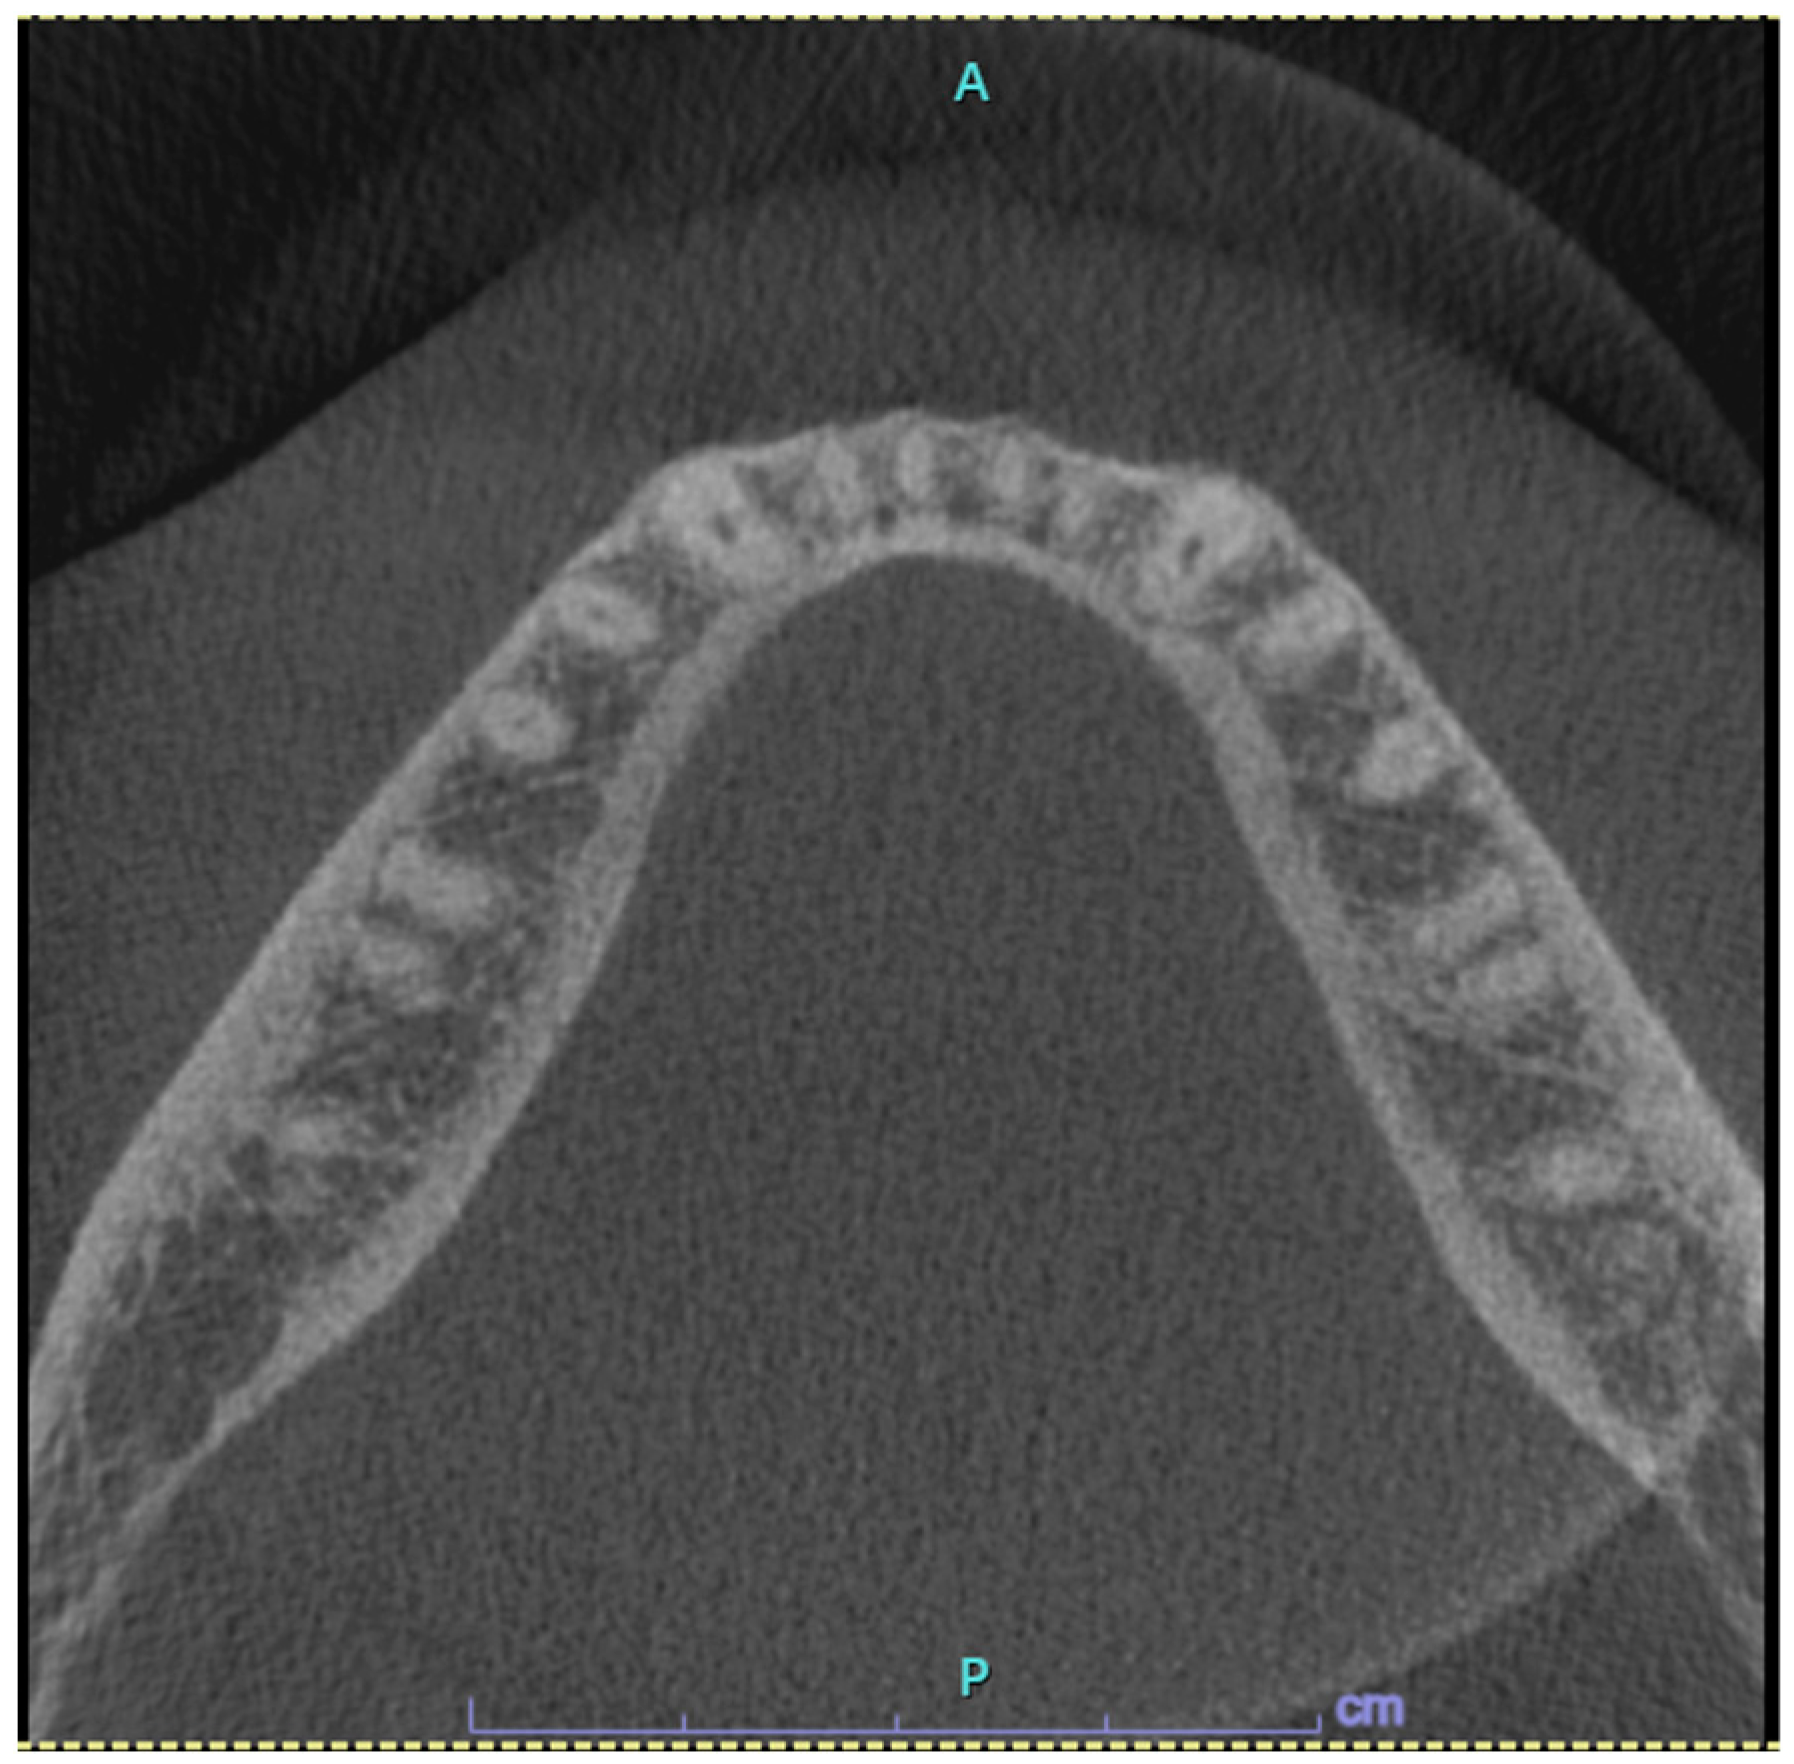

Case Presentation